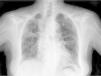

Clinical CaseThe patient is an 83-year-old woman with a history of hypertension treated with amlodipine 5mg/day, chronic kidney disease stage III, secondary to nephrosclerosis (GFR 45ml/min) and chronic treatment of polymyalgia rheumatica with methotrexate 15mg/week, for 4 years approximately. In recent years she has shown good clinical and analytical stability, not requiring steroid therapy or adjustments to her regular medication. Six weeks before admission she progressively presented fatigue, dyspnea, cough, and weight loss of 5kg. She had no fever, joint pain or muscle weakness. On admission, dyspnea at rest was observed with a baseline oxygen saturation of 90%, pulmonary auscultation showed bilateral fine crackles, with no palpable lymphadenopathy or organ enlargement, elevated erythrocyte sedimentation rate of 69mm C-reactive protein 3.5mg/dl and a chest X-ray which highlighted a diffuse and asymmetric bilateral reticular infiltrate with peripheral involvement, worse on the bases and on the right upper lobe (Fig. 1). After making a differential diagnosis of subacute lung disease in the context of methotrexate use, our main approach was to discontinue treatment, start steroids intravenously 48mg/day of methylprednisolone, and support measures, without clear improvement. A high resolution chest CT scan (HRCT) was performed, showing patched interstitial thickening of peripheral predominance in the lung bases and small nonspecific mediastinal lymphadenopathy (Fig. 2). The pulmonary function tests showed forced spirometry values in the low limit of normal, with a forced vital capacity (FVC) 1340ml (82%), a volume of expiratory flow after one second (FEV1) of 1130ml (88%) and an FEV1/FVC ratio of 84%, associated with a severe decrease in lung diffusion of carbon monoxide (DLCO) of 33% and corrected for an alveolar volume (KCO) of 54%. In the rest of the complementary tests, no changes were seen in the blood count, serology for atypical pathogens, the study of tumor markers, blood cultures, the serial study of sputum or the Mantoux/Booster test, so a bronchoscopy was performed with bronchoalveolar lavage (BAL) and led to a positive result in polymerase chain reaction (PCR) testing for CMV associated with an increased rate of CD4/CD8 lymphocytes 3.47, with the rest of the study for common germs, tuberculosis, P. jiroveci and fungi being negative. The microbiological study detected IgG (+), IgM (−) for CMV and CMV viral load in plasma (+), so treatment was initiated intravenously, adjusted for renal function, with ganciclovir 300mg/12h for 14 days, then changing to valganciclovir 900mg/12h orally for 14 days, with good tolerance and clinical response, with improvement in radiological, serological (CMV viral load undetectable) and respiratory function parameters (57.52% DLCO, KCO 80.90%, FVC 1950ml [119%] and FEV1 of 1680ml [130%]).